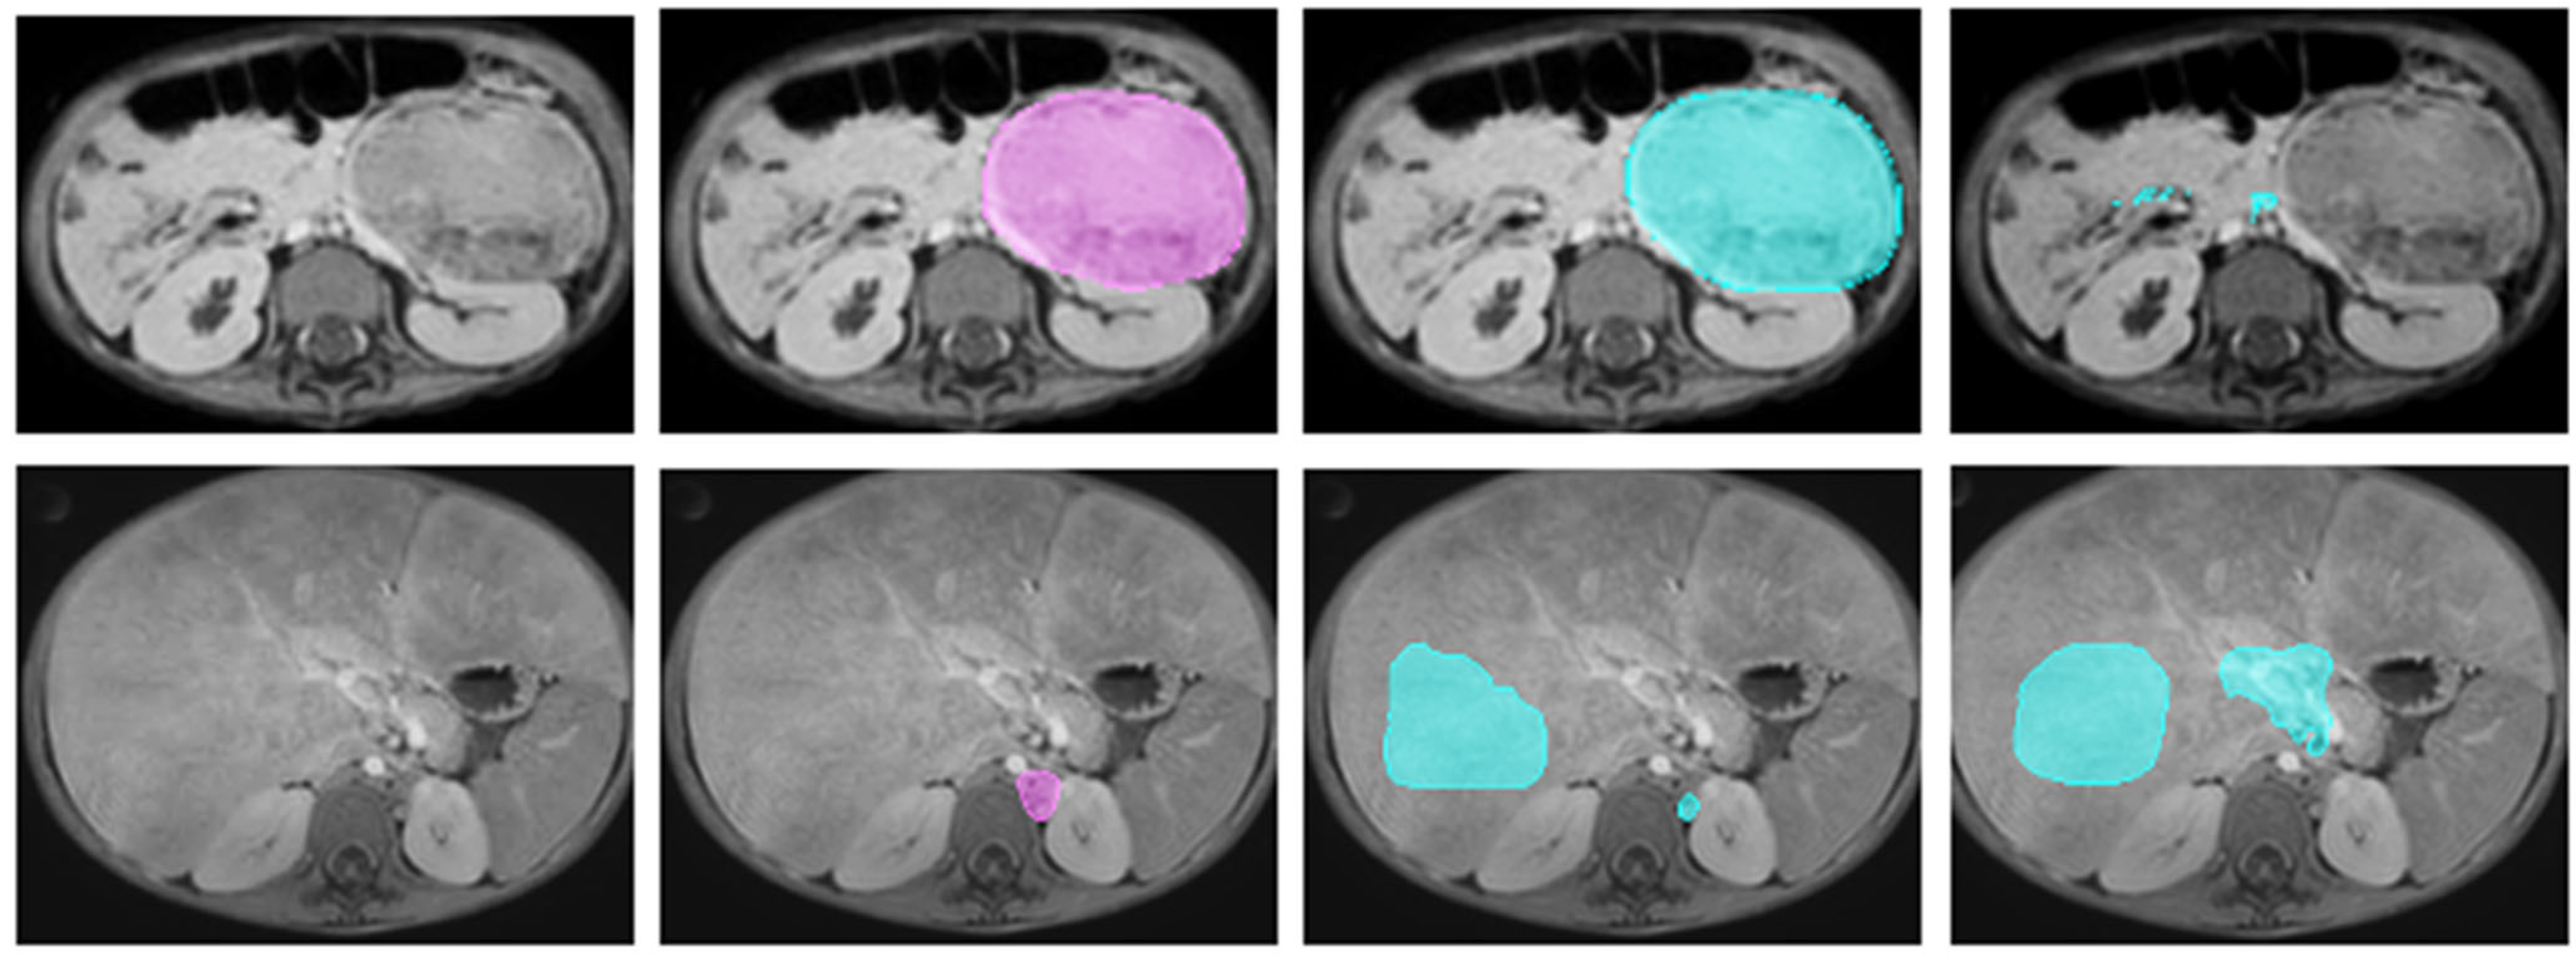

2.2.1. Magnetic Resonance Imaging

2.2.3. Manual Annotation

| Sequence | T1-Weighted Gradient Echo | T2-Weighted Spin Echo | Diffusion-Weighted Imaging |

|---|---|---|---|

| Repetition time (ms) | 6.1 | 458 | 2537 |

| Echo time (ms) | 2.9 | 90 | 76.4 |

| Voxel size (mm3) | 0.71 × 0.71 × 3 | 0.833 × 0.833 × 1.15 | 1.39 × 1.39 × 5 |

| Dimensions (voxels) | 560 × 560 × Z | 480 × 480 × Z | 288 × 288 × Z |

| b-values (s/mm2) | N/A | N/A | 0, 100 |

| Contrast | Gadovist, 0.1 mmol/kg body weight | - | - |